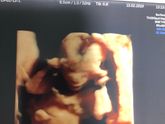

❤️узи 30 недель ❤️

Сходили сегодня на узи, мне интересно было узнать вес и перевернулась ли моя дочка в правильное положение. Так вот такие итоги: узист попался мужчина, но все понятно и толково разъяснял. Срок опережаем на 2 дня. Вес 1647?? пульс ? 137 ударов, дочка перевернулась … Читать далее